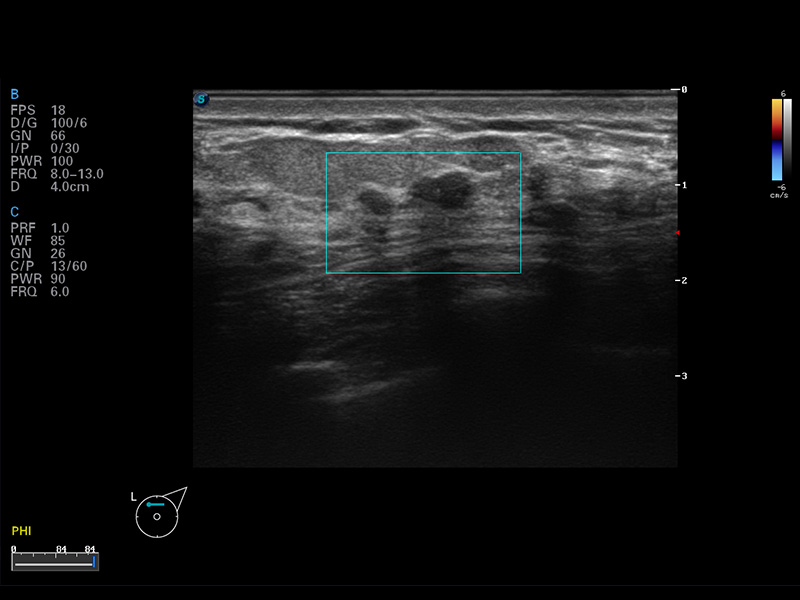

S8 EXP便携式彩色多普勒超声诊断仪是环球UG官网研发的高端全身应用型便携彩超。高通道的VIS平台融合可视化(Visual)、智能化(Intelligent)和人性化(Smart)的特点,配以环球UG官网自主研发生产的探头大家族,使您能够快速、准确的获得病人信息,提高工作效率的同时减轻疲劳。

成像技术

多波束形成器

μ-Scan微米成像

谐波成像

实时宽景成像

空间复合成像